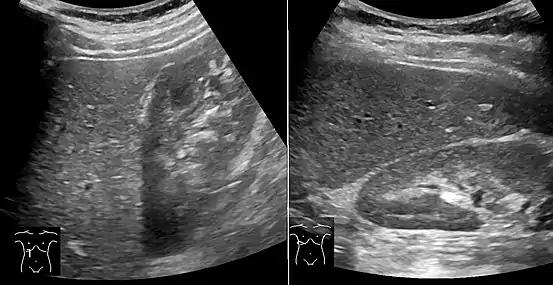

On X-ray computed tomography (CT), the increased fat component will decrease the density of the liver tissue, making the image less bright. Typically the density of the spleen and liver are roughly equivalent. In steatosis, there is a difference between the density and brightness of the two organs, with the liver appearing darker.[12] On ultrasound, fat is more echogenic (capable of reflecting sound waves). The combination of liver steatosis being dark on CT and bright on ultrasound is sometimes known as the flip flop sign.

On abdominal ultrasonography, steatosis is seen as a hyperechoic liver as compared to the normal kidney.

- Abdominal ultrasonography with the liver and kidney side by side (left image) may give a false impression of hyperechogenic liver, so it's preferably done with the organ borders facing the ultrasound probe (right image, of the same case).